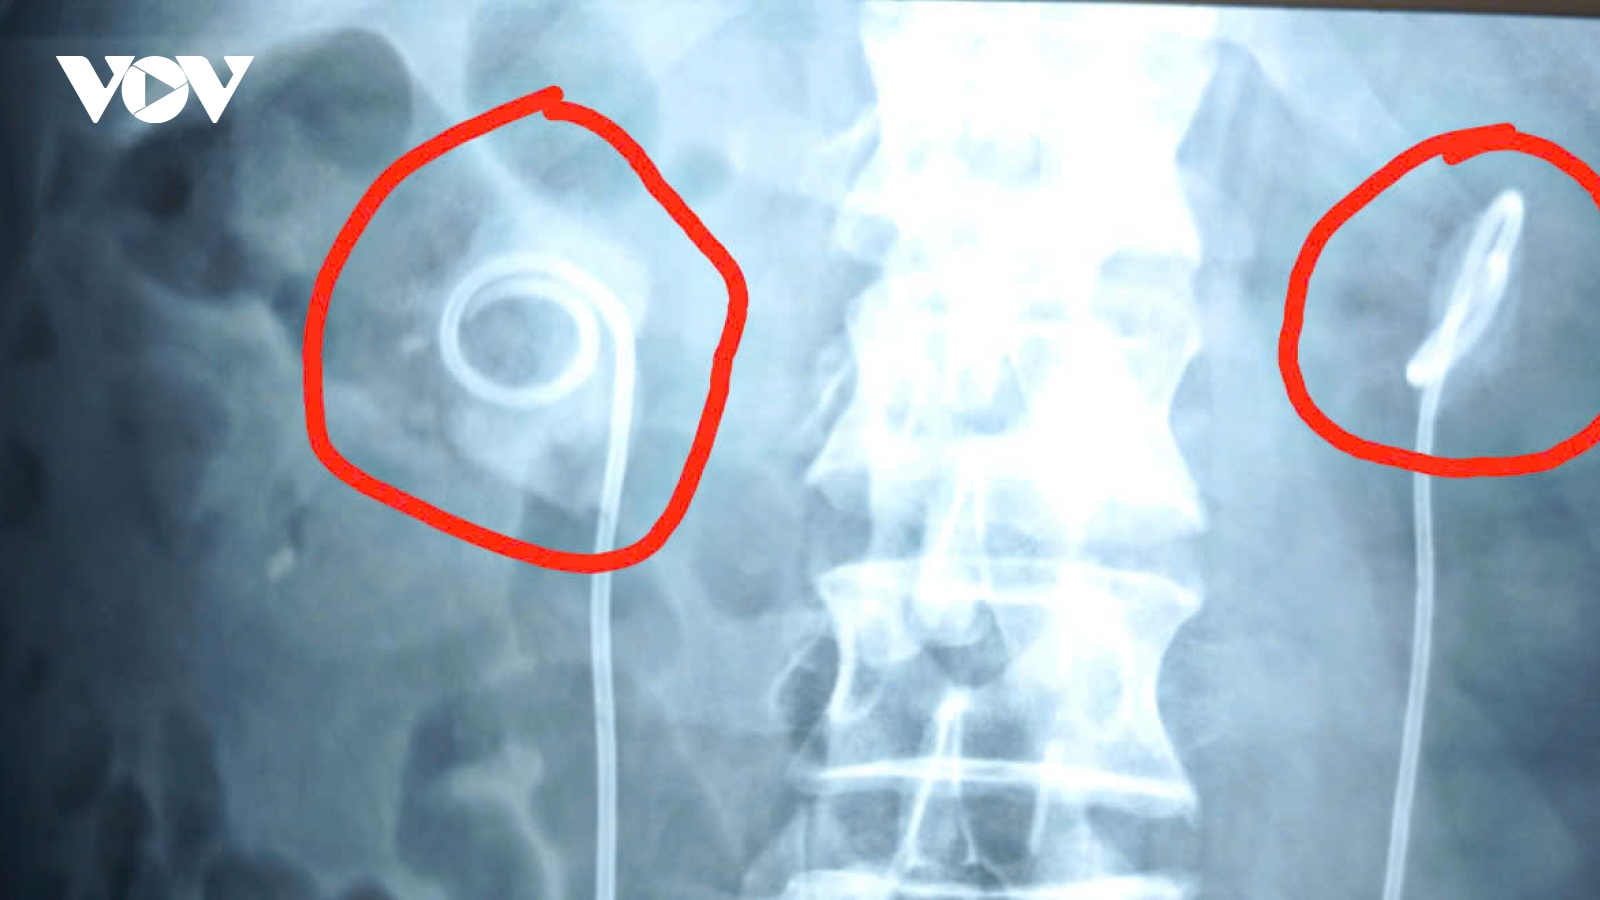

Hai ca biến chứng nặng do tiêm filler mông giá rẻ

VOV.VN - Bác sỹ khuyến cáo, những chất làm đầy không rõ nguồn gốc có thể gây viêm kéo dài, tái phát nhiều lần, để lâu có thể hình thành u hạt, xơ cứng và rất khó điều trị. Người dân tuyệt đối không tiêm filler tại spa hoặc cơ sở thẩm mỹ không phép, các sản phẩm làm đẹp trôi nổi, rao bán giá rẻ trên mạng